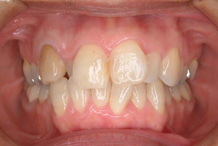

正面から観たところです。

全て乳歯です。反対咬合です。まだ幼児なので、お子様にかかる負担などをよく考えた上で、治療します。

反対咬合です。